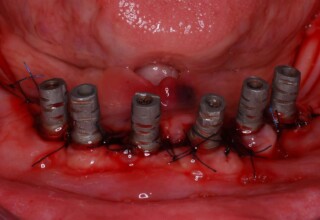

Full mouth prosthetic reconstruction on implants with a different approach on upper and lower jaw

Lower jaw: extractions, direct implant placement and immediate loading (same day) with a transitional bridge.

Upper jaw: Sequential extractions, sequential implant placement and gradual incorporation in the temporary bridge so that the patient was never left without fixed teeth. The aim of the above approach was to have the patient in continuous functional and aesthetic reconstruction, without immediate loading due to anatomical restrictions. Old smiling photos of the patient were used because the natural shape of the teeth was completely lost due to repetitive prosthetic attempts. Tooth relationship and teeth-lip support was transferred to the temporary restorations. Two different transitional bridges were needed to fully estimate phonetics, mastication and esthetics. After the necessary adjustments were finalized, the temporary bridge was used as a guide for the permanent bridges.

Intermediate